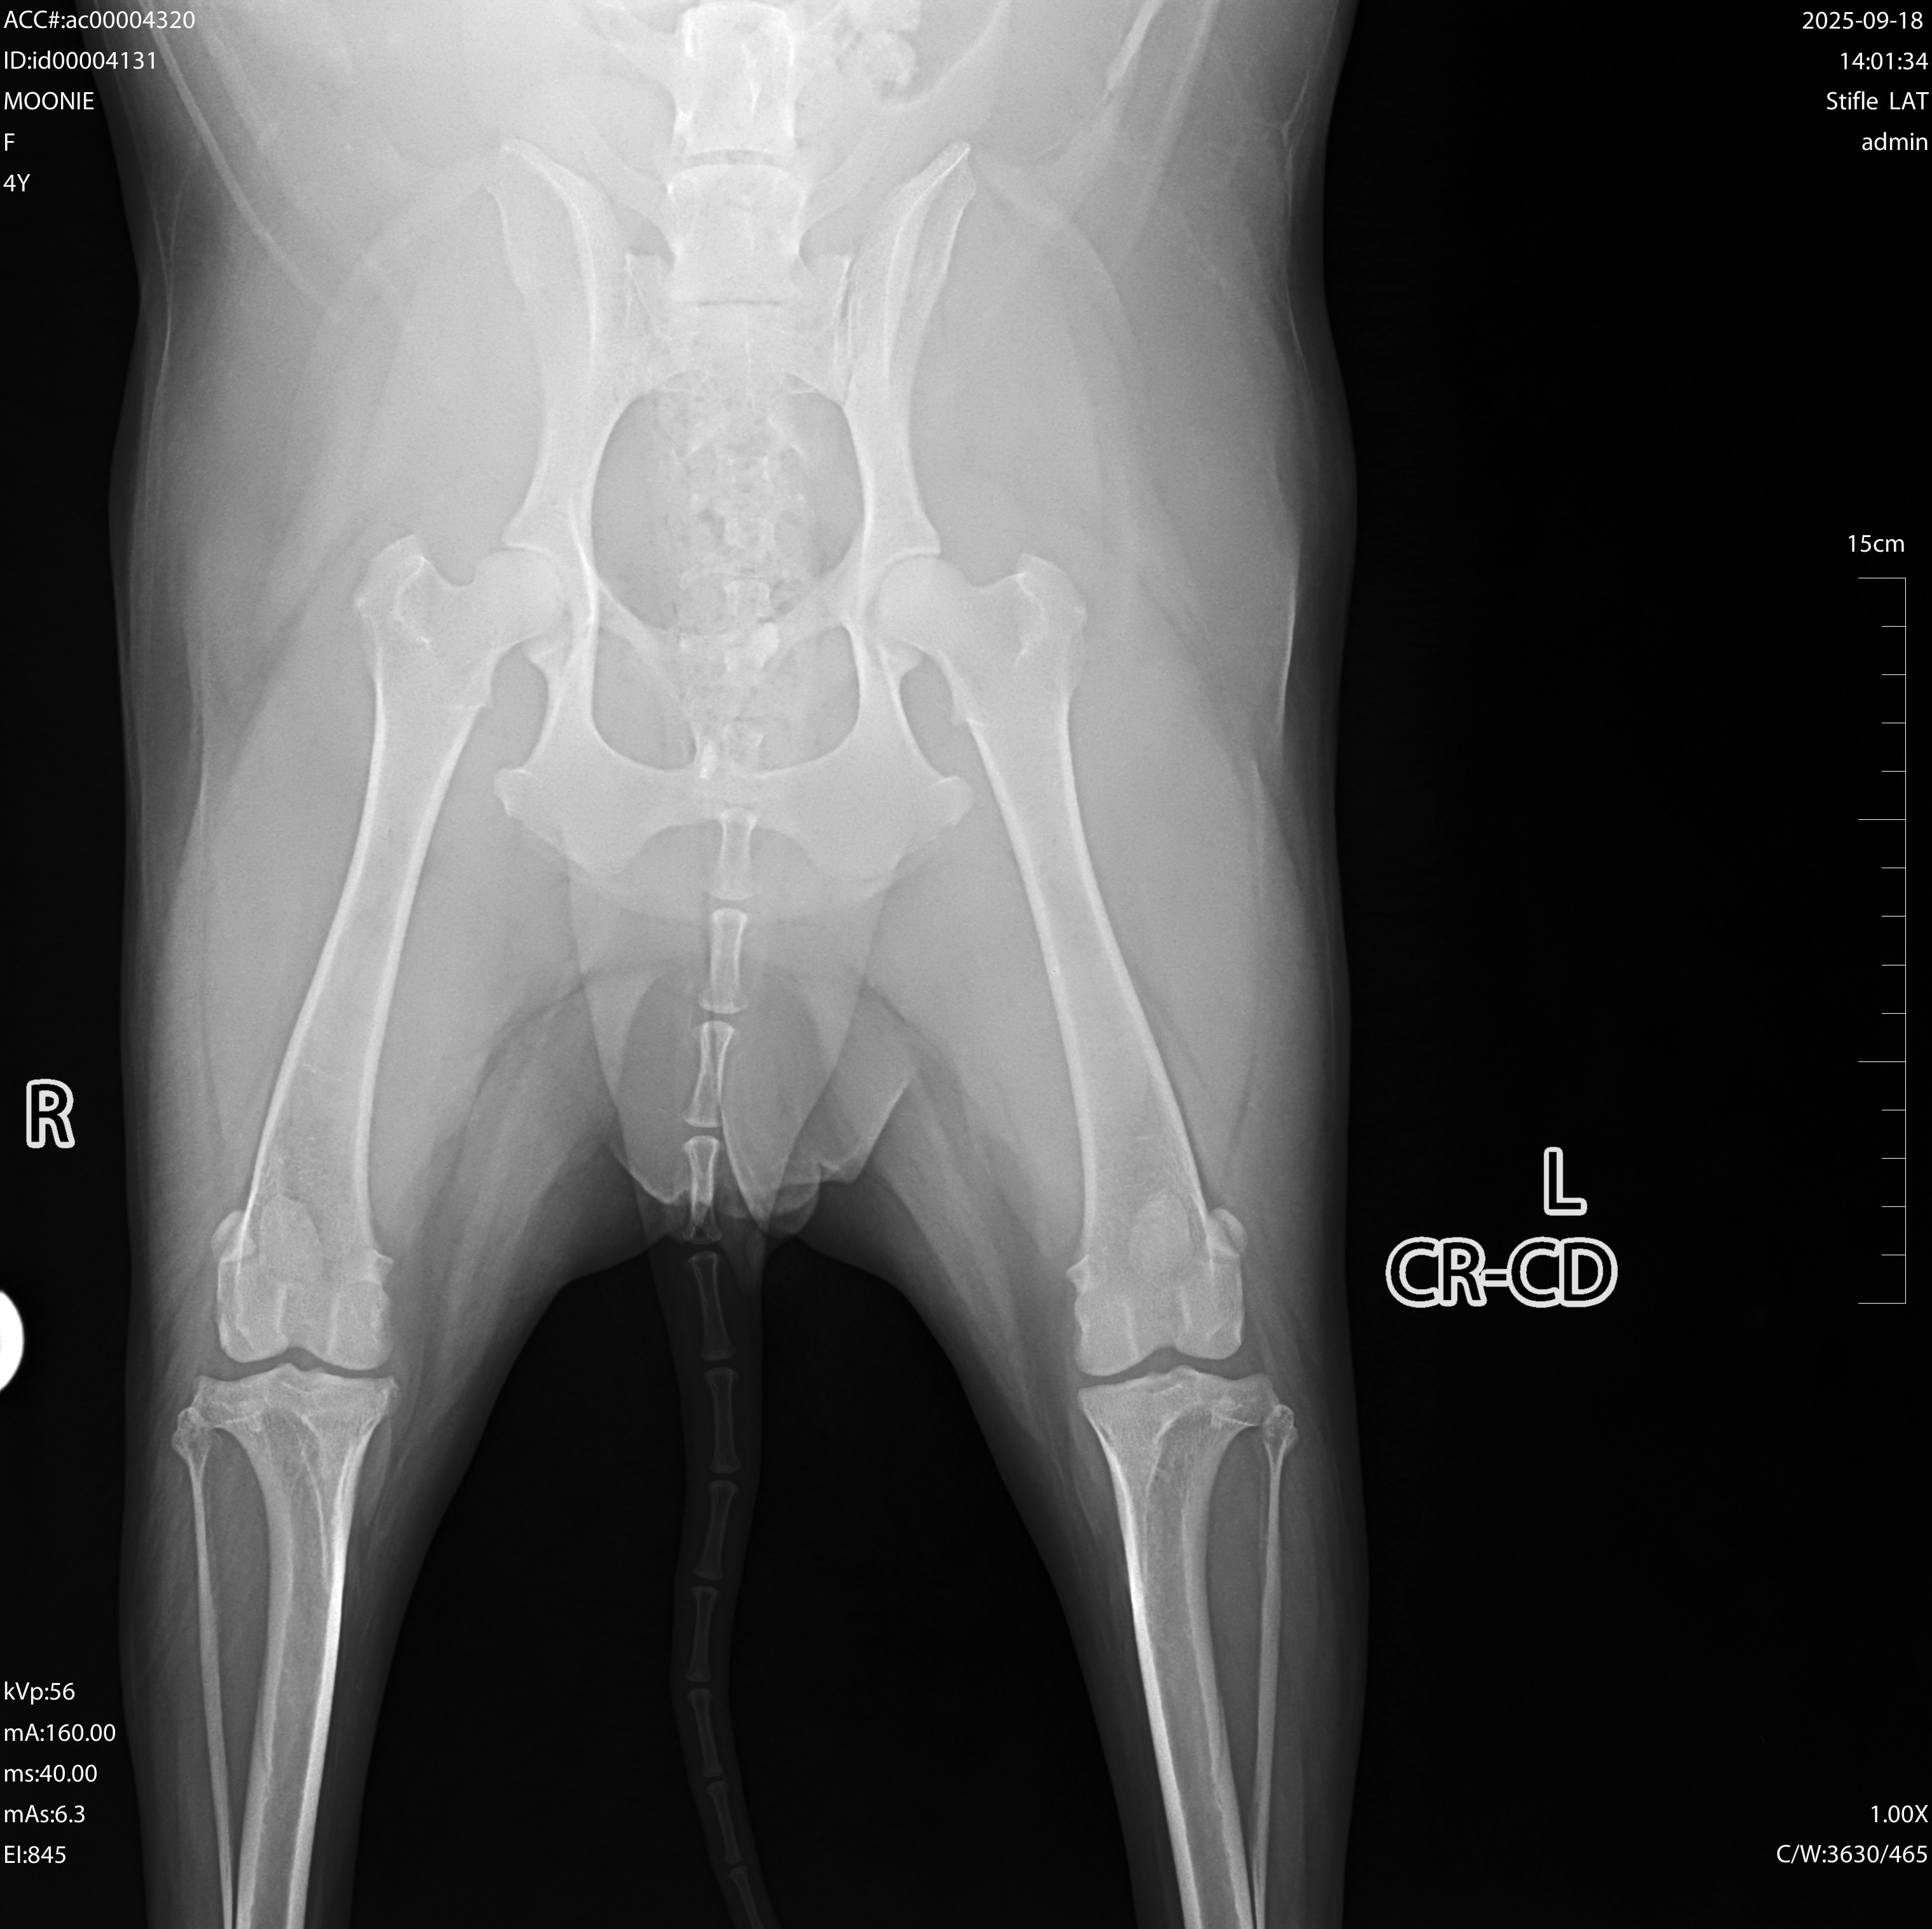

Hello, my name is Giovanna, and I’m raising funds for my beloved dog, who desperately needs ACL surgery. She is more than a pet ❤️; she is my family. She sleeps by my side every night and has been companion for four years. I want to give her the healthy, pain-free life she deserves.

I live in Imperial CA, and unfortunately, there are no veterinary specialists here who can perform the surgery my dog needs. My only option nearby was to try clinics in Mexicali, Mexico. In the past, when I lived in San Diego, I had good experiences in Tijuana, so I trusted it would be the same. Sadly, this time I was scammed. I’ve already spent about $500 on consultations, medications, x-rays, and bloodwork, but the clinics kept canceling appointments and surgeries, and my dog still hasn’t received the care she needs.

My dog is still young, only four years old, and I pray she has many more happy years ahead. Any donation, big or small, will go directly toward her surgery and recovery. Your support means everything to me, and it would relieve the heavy stress of not knowing if I can give her the care she needs.